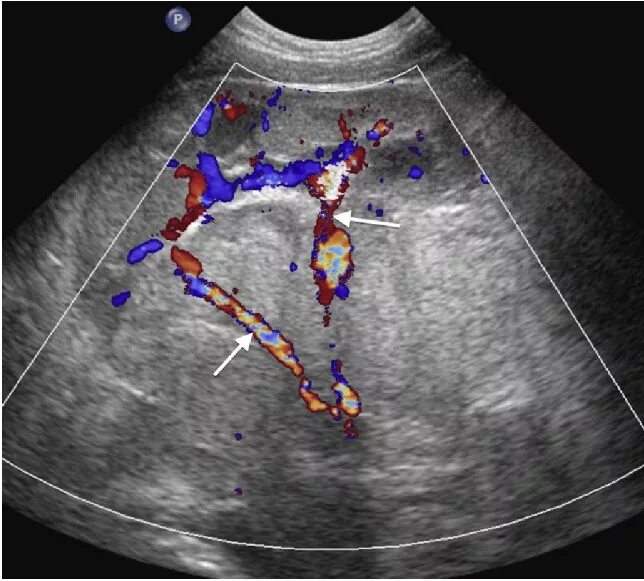

Узи надпочечников и забрюшинного пространства подготовка